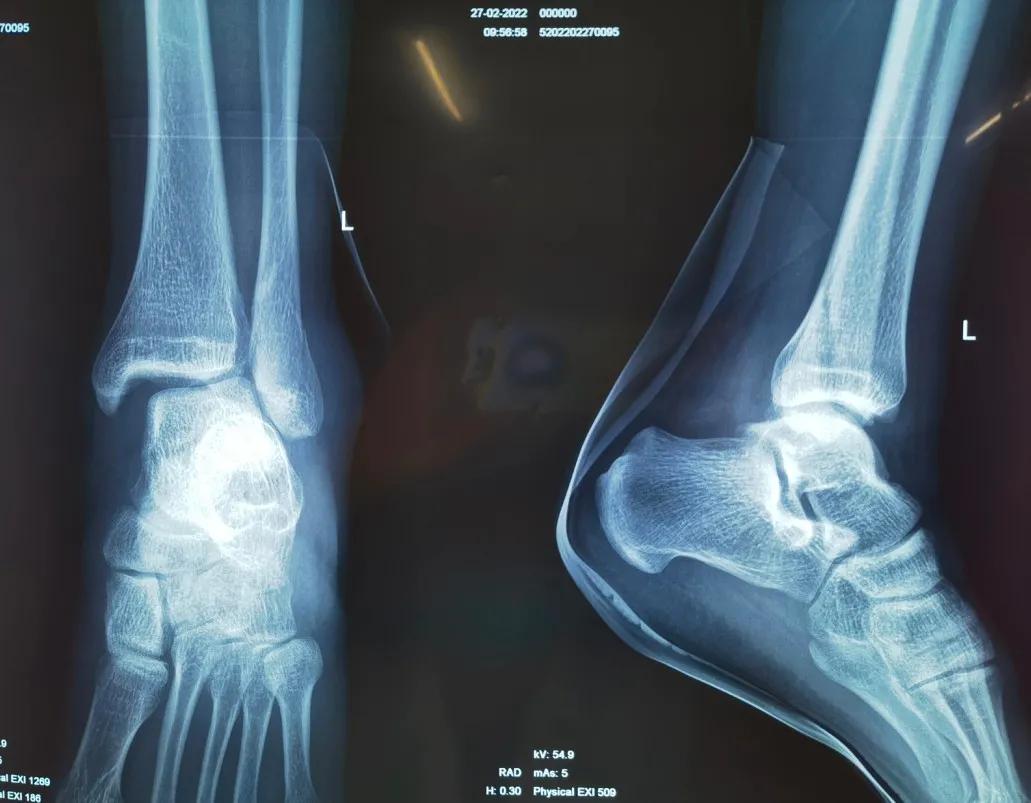

踝关节骨折,需不需要手术?一文总结踝关节骨折的治疗目标及方法

踝关节骨折是常见的创伤,约占所有成人骨折的10%。这种损伤不仅影响患者的日常生活,还可能导致长期的关节功能障碍。因此,及时、恰当的治疗至关重要。

踝关节骨折的治疗需要基于准确的评估和分型。临床上常用的分型方法包括Lauge-Hansen分型和Danis-Weber分型。Lauge-Hansen分型根据损伤机制将踝关节骨折分为旋后-内收、旋后-外旋、旋前-外展、旋前-外旋四种类型。而Danis-Weber分型则根据腓骨骨折的位置不同分为A、B、C三型。这两种分型方法各有特点,临床实践中往往需要结合使用。